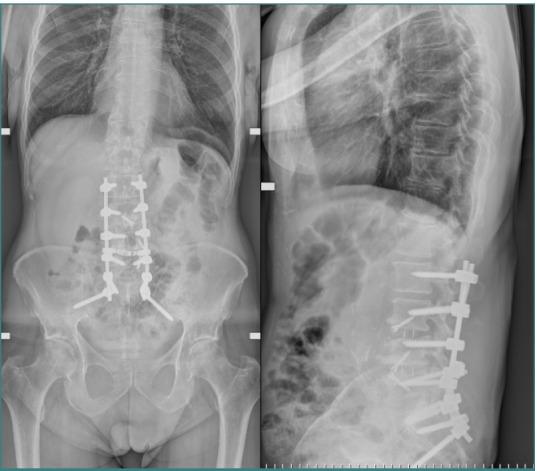

Vascular injuries during anterior lumbar interbody fusion (ALIF) are reported in the existing literature with an incidence rate ranging from 1% to 24%, predominantly venous lacerations owing to branch vessel avulsions during mobilization and retraction. Arterial injuries, although less frequent, occur at an incidence of 0.45% to 1.5% and are mainly characterized by thromboses; aortic lacerations remain exceptionally rare. L4-L5 and L5-S1 are the two levels associated with the majority of vascular complications. Preoperative 3D CT angiography is paramount and a gold standard, as it illustrates the anatomic variations of the iliolumbar vein, the aorta, and the vena cava bifurcation, providing the surgeon with valuable information regarding operative trajectories. Regarding preventive measures, venous laceration, the most common vascular injury, occurs less frequently when employing nonthreaded interbody grafts such as iliac crest autograft or femoral ring allograft. Also, left iliac artery thrombosis can be decreased intraoperatively by intermittent release of retraction. Managing vascular complications includes compression for bleeding control, Trendeleburg positioning of the patient and venorrhaphy, and the employment of topical clot-forming enhancement and/or hemostatic agents. Although postoperative lower limb duplex ultrasonography can be an effective tool, magnetic resonance venography (MRV) and intravenous catheterization (IVC) remain the gold standards for diagnosing postoperative pelvic vein thrombosis in cases of iliac vein repair after anterior spine surgery. This paper aimed to highlight the incidence of major vascular injury during ALIF surgery, describe predisposing risk factors, and discuss management techniques while highlighting the requirement for more sensitive and factor-specific studies to attain a more profound understanding of the mechanism of vasculature complications during ALIF procedures.

现有文献报道了腰椎前路椎间融合术(ALIF)期间血管损伤的发生率在1%至24%之间,主要是由于在松动和牵开过程中分支血管撕脱导致的静脉撕裂。动脉损伤虽然较少见,发生率为0.45%至1.5%,主要表现为血栓形成;主动脉撕裂极为罕见。L4-L5和L5-S1是与大多数血管并发症相关的两个节段。术前三维CT血管造影至关重要,是金标准,因为它能显示髂腰静脉、主动脉和腔静脉分叉的解剖变异,为外科医生提供有关手术路径的有价值信息。关于预防措施,使用非螺纹椎间融合器(如髂嵴自体骨移植或股骨环同种异体移植)时,最常见的血管损伤——静脉撕裂的发生率较低。此外,术中通过间歇性松开牵开可减少左髂动脉血栓形成。处理血管并发症包括压迫止血、患者头低脚高位和静脉缝合,以及使用局部促凝增强剂和/或止血剂。虽然术后下肢双功超声检查可能是一种有效的工具,但磁共振静脉造影(MRV)和静脉插管(IVC)仍然是诊断前路脊柱手术后髂静脉修复病例中术后盆腔静脉血栓形成的金标准。本文旨在强调ALIF手术期间主要血管损伤的发生率,描述易感危险因素,并讨论处理技术,同时强调需要进行更敏感和针对特定因素的研究,以更深入地了解ALIF手术期间血管并发症的机制。